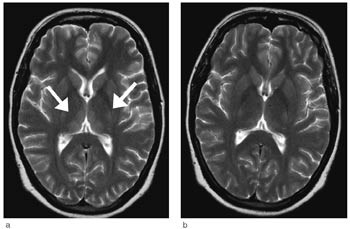

EEG viste uspesifikk langsom aktivitet over begge hemisfærer uten tegn på encefalitt. Cerebral CT viste normale forhold. Da pasientens bevissthetsnivå var redusert og fordi tilstanden var uavklart, ble det funnet indikasjon for MR-undersøkelse av cerebrum samme natt. Undersøkelsen viste bilaterale symmetriske lesjoner i mediale thalamus, corpora mammillaria, den periakveduktale gråe substans og i bunnen av 4. ventrikkel, forenlig med Wernickes encefalopati (fig 1).

Omfattende utredning viste i løpet av kort tid at det forelå en encefalopati med konfusjon som hovedsymptom og som maskerte andre nevrologiske symptomer. Pga. langvarig hyperemesis over flere uker ble Wernickes encefalopati en viktig differensialdiagnose. MR-undersøkelse av cerebrum bekreftet denne diagnosen.

Vi baserte diagnosen på den nevnte triaden konfusjon, øyemuskelpareser og ataksi samt karakteristiske MR-funn (10). Denne pasienten hadde symmetriske områder med forhøyet T2-signal i dorsomediale thalamus, periakveduktalt i mesencefalon, i hypothalamus og i corpora mammillaria, noe som er typisk for Wernickes encefalopati (10) – (12). Hos enkelte pasienter vil man se kontrastopptak i disse lesjonene, men dette er ikke obligat. Hos vår pasient ble det ikke gitt intravenøs kontrast. Diffusjonsvektede MR-bilder er en sensitiv metode for å påvise intracellulært ødem hvor diffusjonen er redusert. Ved hjerneinfarkter betyr redusert diffusjon som regel en irreversibel vevsskade, som utvikles til nekrose. Det er de siste årene kommet flere rapporter som viser at enkelte av pasientene med Wernickes encefalopati har redusert diffusjon i mediale thalamus (11, 12). I utgangspunktet vil et slikt MR-funn indikere en alvorligere prognose med større risiko for vevshenfall. Hos vår pasient ble det ikke påvist redusert diffusjon. Det er også typisk å se en tydelig tilbakegang av signalforandringene ved MR-undersøkelse etter få dagers behandling med tiamin (10). Hos vår pasient observerte vi dette. Ved den første kontrollundersøkelsen var det en begynnende normalisering, og etter 2 1/2 måneder var normaliseringen fullstendig.